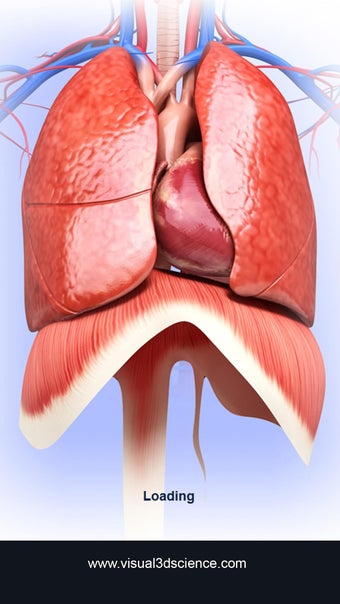

呼吸器系の解剖学は、肺、気管、およびすべての気道を含む呼吸器系の解剖学の研究です。最も一般的なアプローチは、系を上部と下部に分割することです。上部には気管、主気管支、および終末および前頸気道が含まれます。下部には肺と最小の大きさの末梢気道が含まれます。これらの部分それぞれには特徴的な外観と機能があります。

このアプリケーションは、高度にリアルな呼吸器系のモデルです。ユーザーは任意の角度および任意の平面から呼吸器系の解剖学を表示できます。ユーザーは360°回転し、ズームインおよびズームアウトして解剖学をよりよく研究することができます。ユーザーはまた、画面に描画するためのさまざまなツールを使用して写真を撮ることもできます。